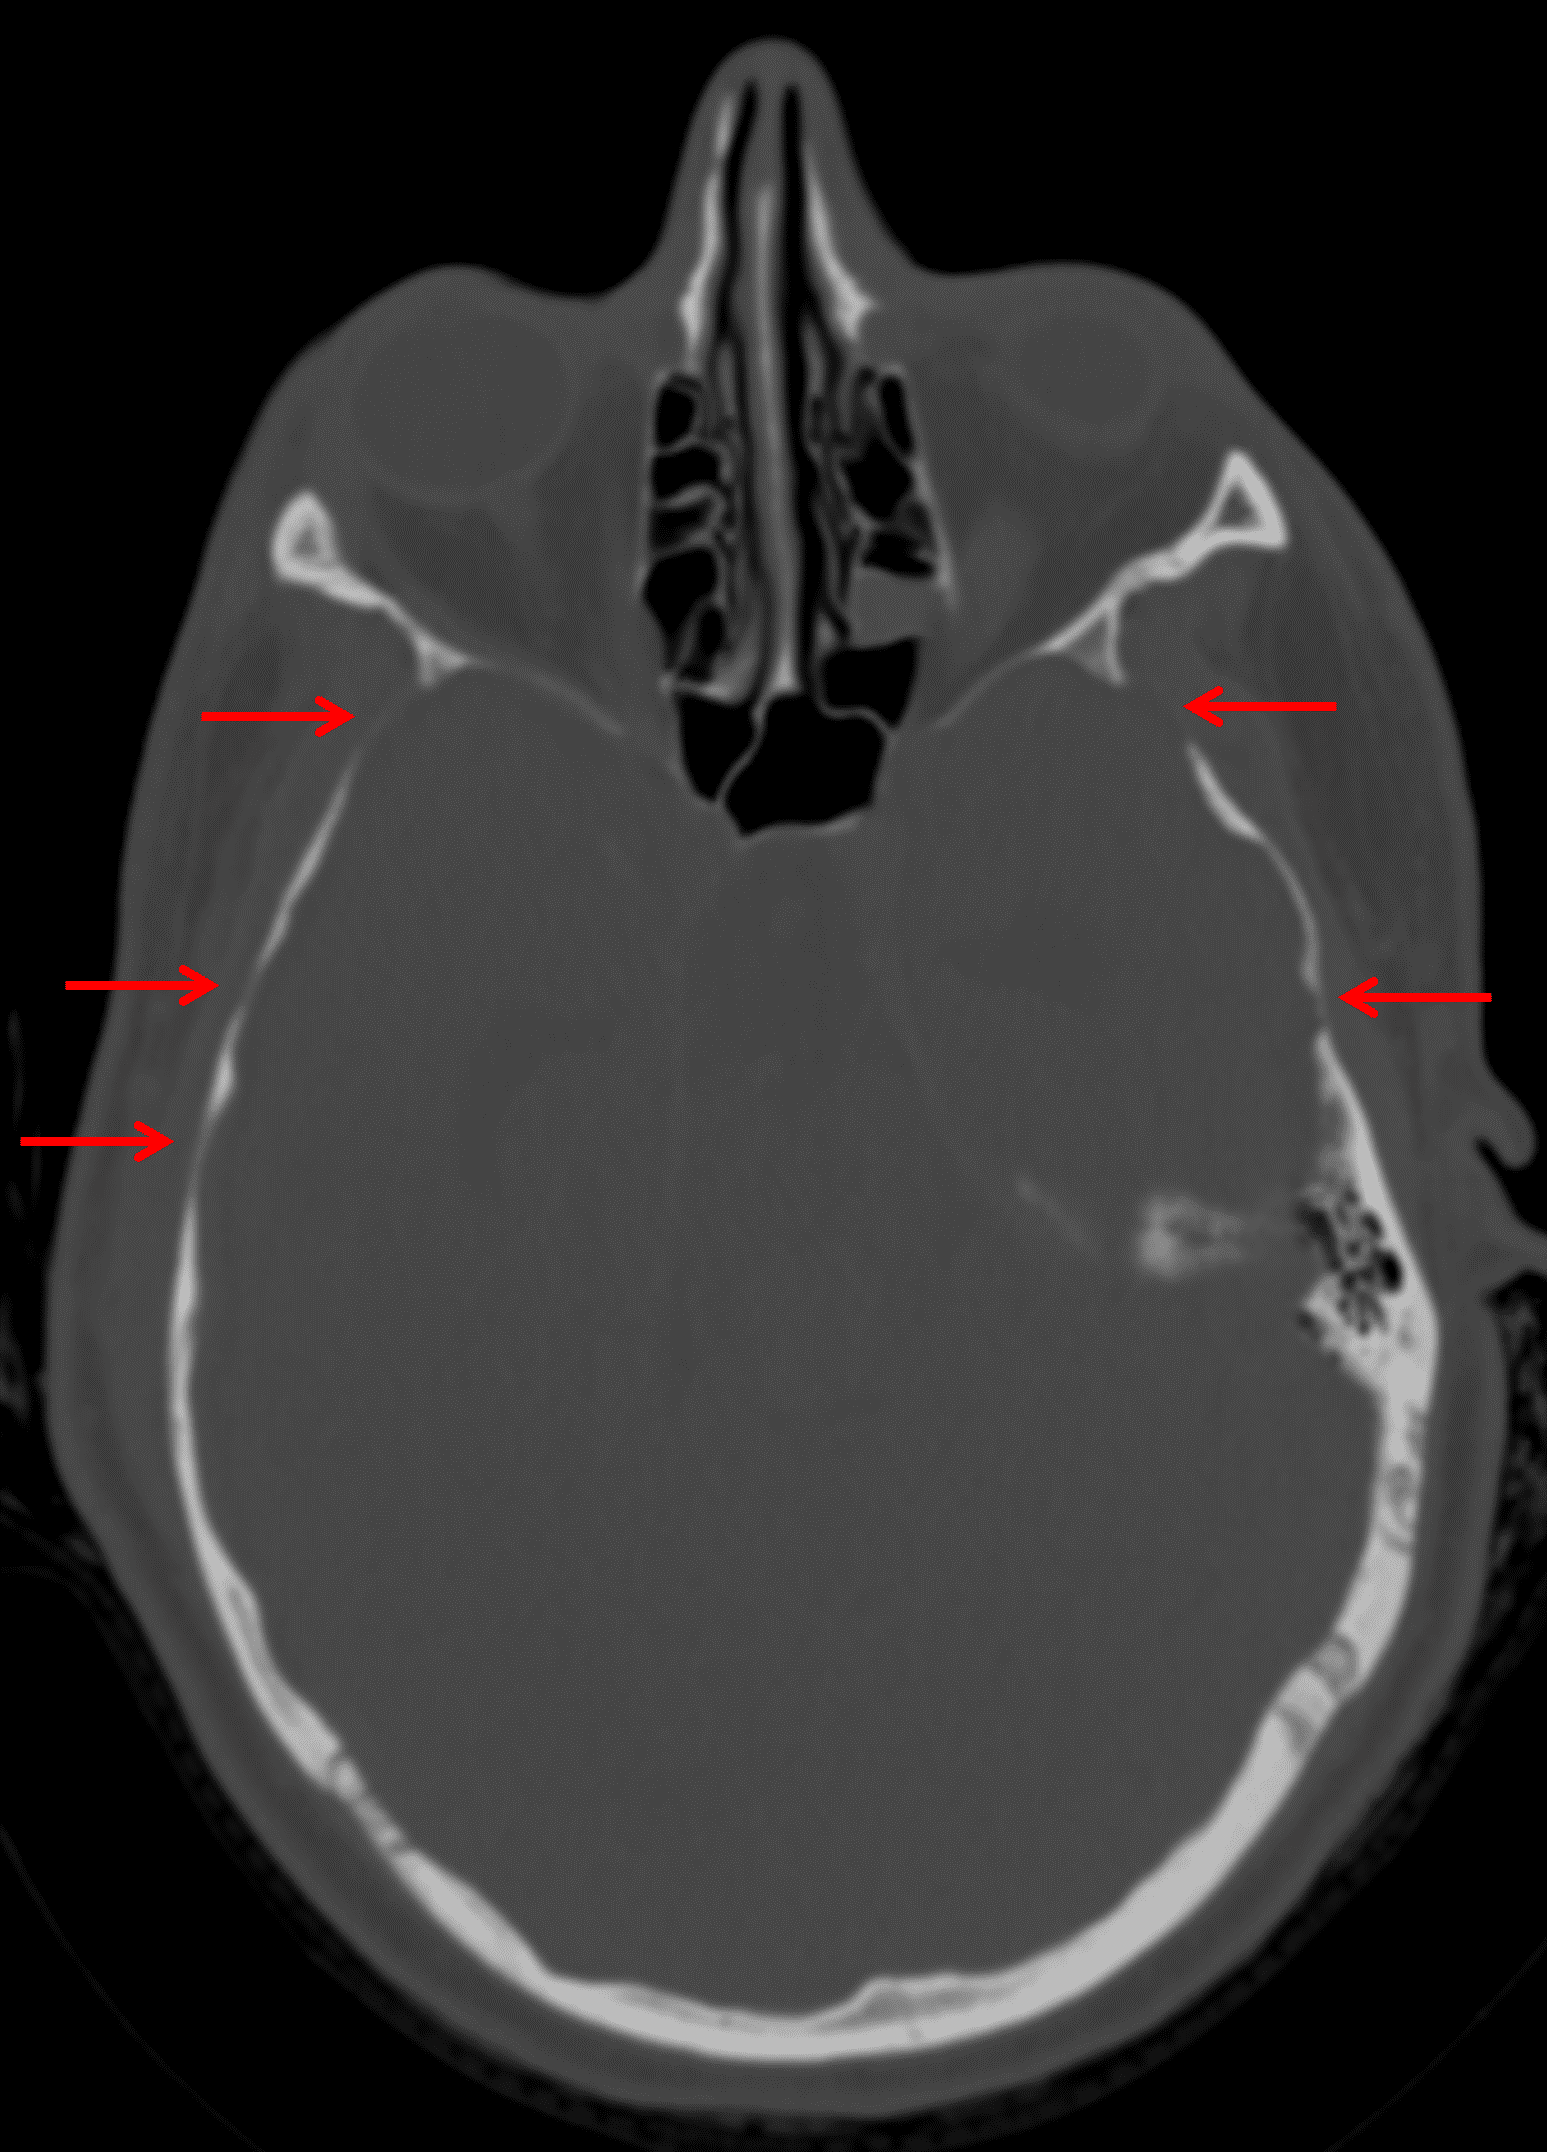

- Multifocal areas of calvarial thinning, particularly involving the bilateral greater sphenoid wings and squamous temporal bones and the cribriform plate

Multiple areas of calvarial thinning (red arrows), likely the result of longstanding elevated intracranial pressure.